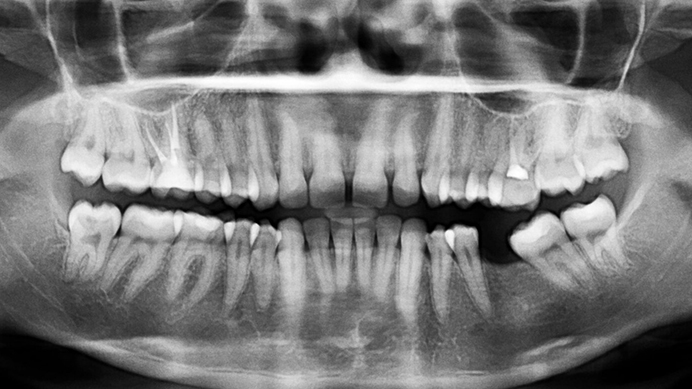

レントゲン

上下の歯列全体を一枚の画像で撮影します。歯の位置関係や親知らずの状態、これまでの治療痕など、お口全体のデータを取得するための基本的な検査です。